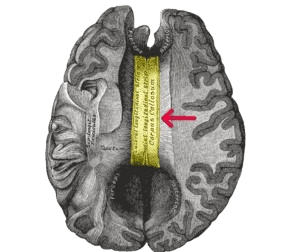

Corpus Callosotomy is a surgical procedure to treat epilepsy. Epilepsy, which is a chronic medical condition, affects individuals for the long term and leads to recurrent seizures in both children and adults. Typically, the treatment is performed under the care of the best neurosurgeons in India. During the corpus callosotomy procedure, an incision is made through the brain's corpus callosum. The corpus callosum, which is a type of band of nerve fibers, joins the two halves of the brain (hemispheres) and relays messages from one hemisphere to the other. As a result, the corpus callosum prevents seizure signals from crossing back and forth between the two hemispheres, thus limiting the spread of seizure activity. This surgery is also known as callosal sectioning or brain splitting.

The corpus callosum, which is a type of band of nerve fibers, joins the two halves of the brain (hemispheres) and relays messages from one hemisphere to the other.